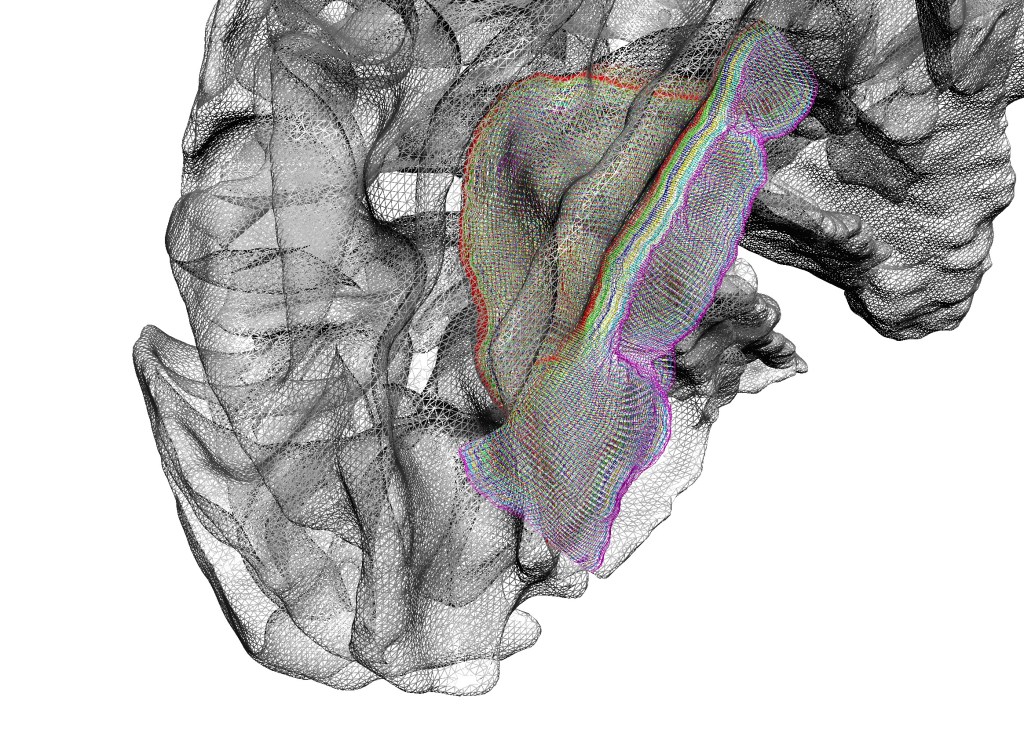

7T -Layer – fMRI